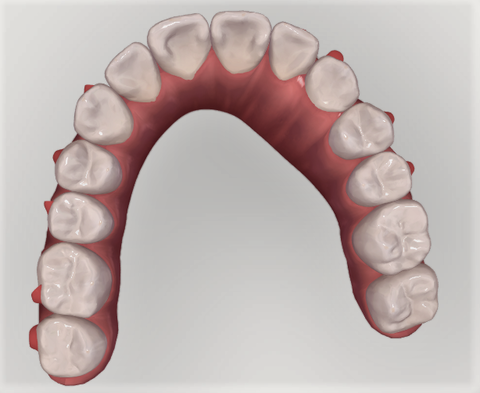

下の歯にも同様に引っ込んだ歯がある。

下の歯。こちらも歯並びの中に納まっている。

下の歯の比較